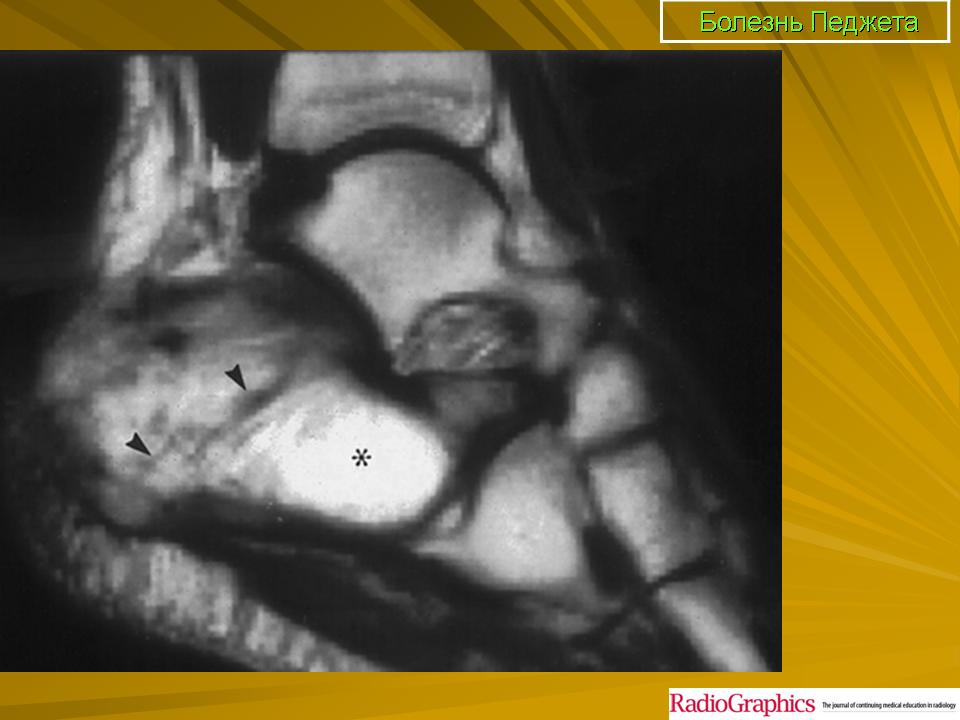

Литическая фаза.

Смешанная фаза.

Бластная фаза

Принято различать три фазы развития П. б.: очаговая интенсивная резорбция кости (остеолитическая, или деструктивная, фаза), смешанная фаза, когда наряду с рассасыванием кости идут процессы новообразования ее, и остеобластическая, или склеротическая, фаза с образованием типичных мозаичных структур.